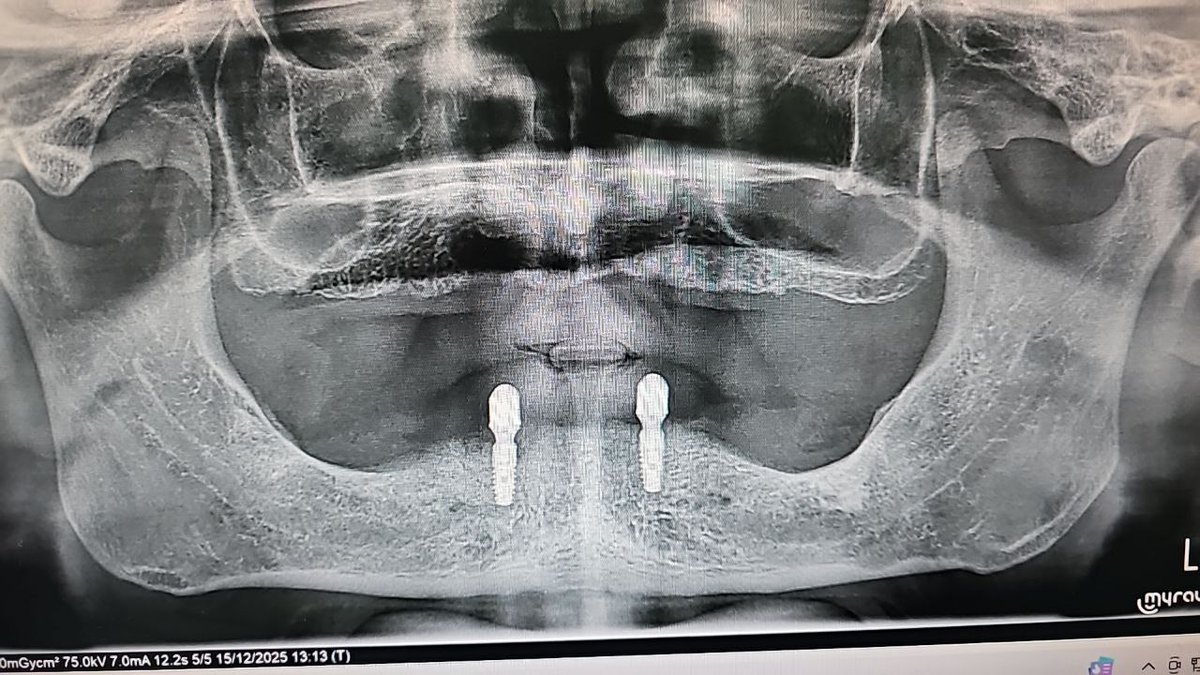

Soluğu acilde alan bir adam, çenesinin nasıl çıktığını paylaştı: